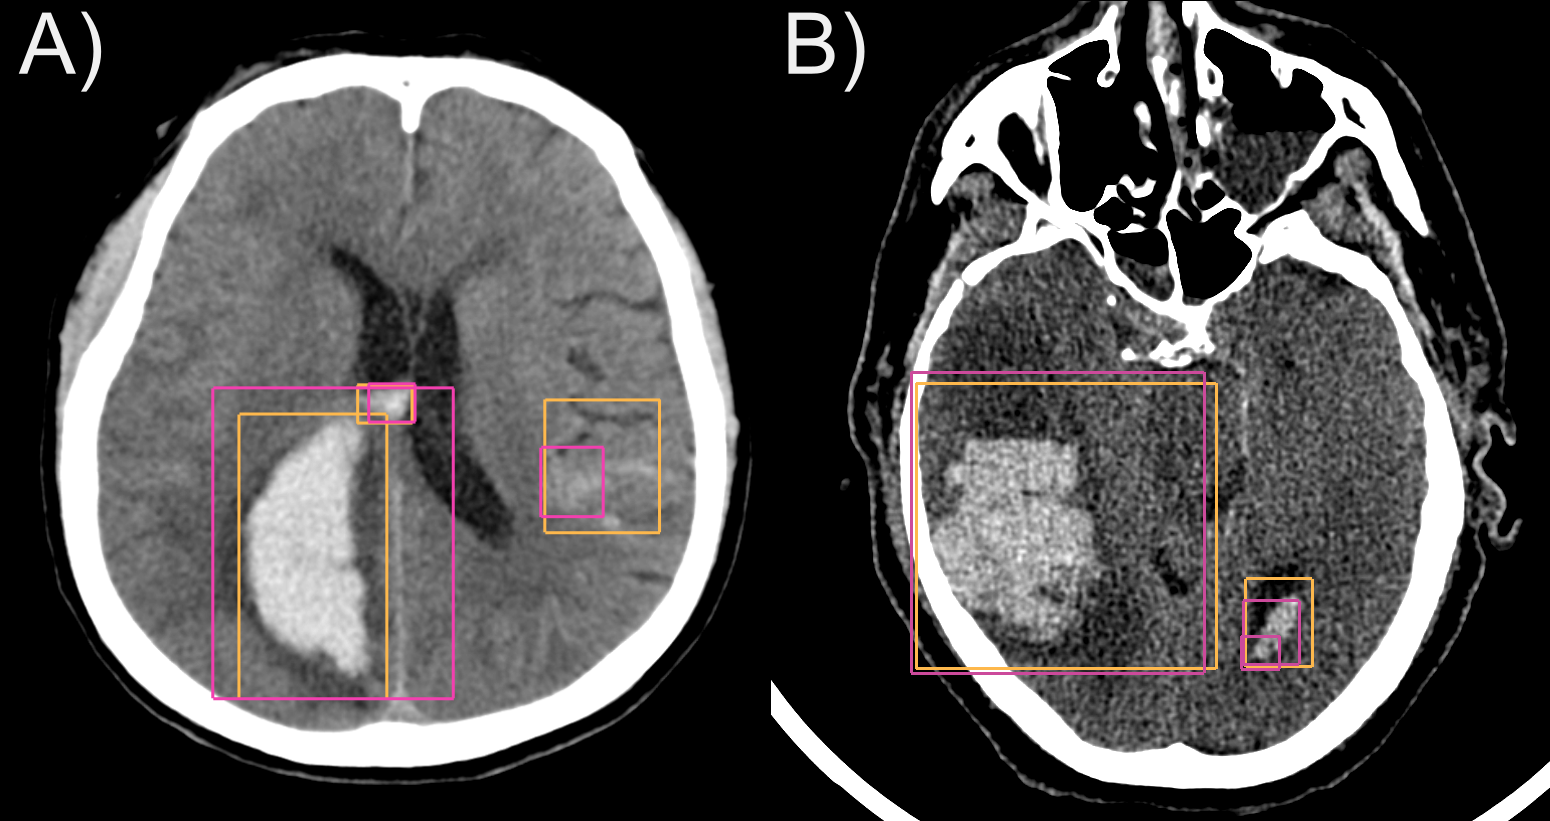

We first evaluate our method against state-of-the-art solutions. As shown in Table 1, our method significantly outperforms both nnDetection and nnU-Net on both datasets. nnU-Net comes last, showing how segmentation is inadequate for object detection. While there is a drop in performance on the private cohort for all methods, ours is more robust against distribution shifts. The FROC analysis (Fig. 6) sheds some further light on the difference in performance between datasets for each method. Additionally, we provide some qualitative results for our method in Fig. 7.